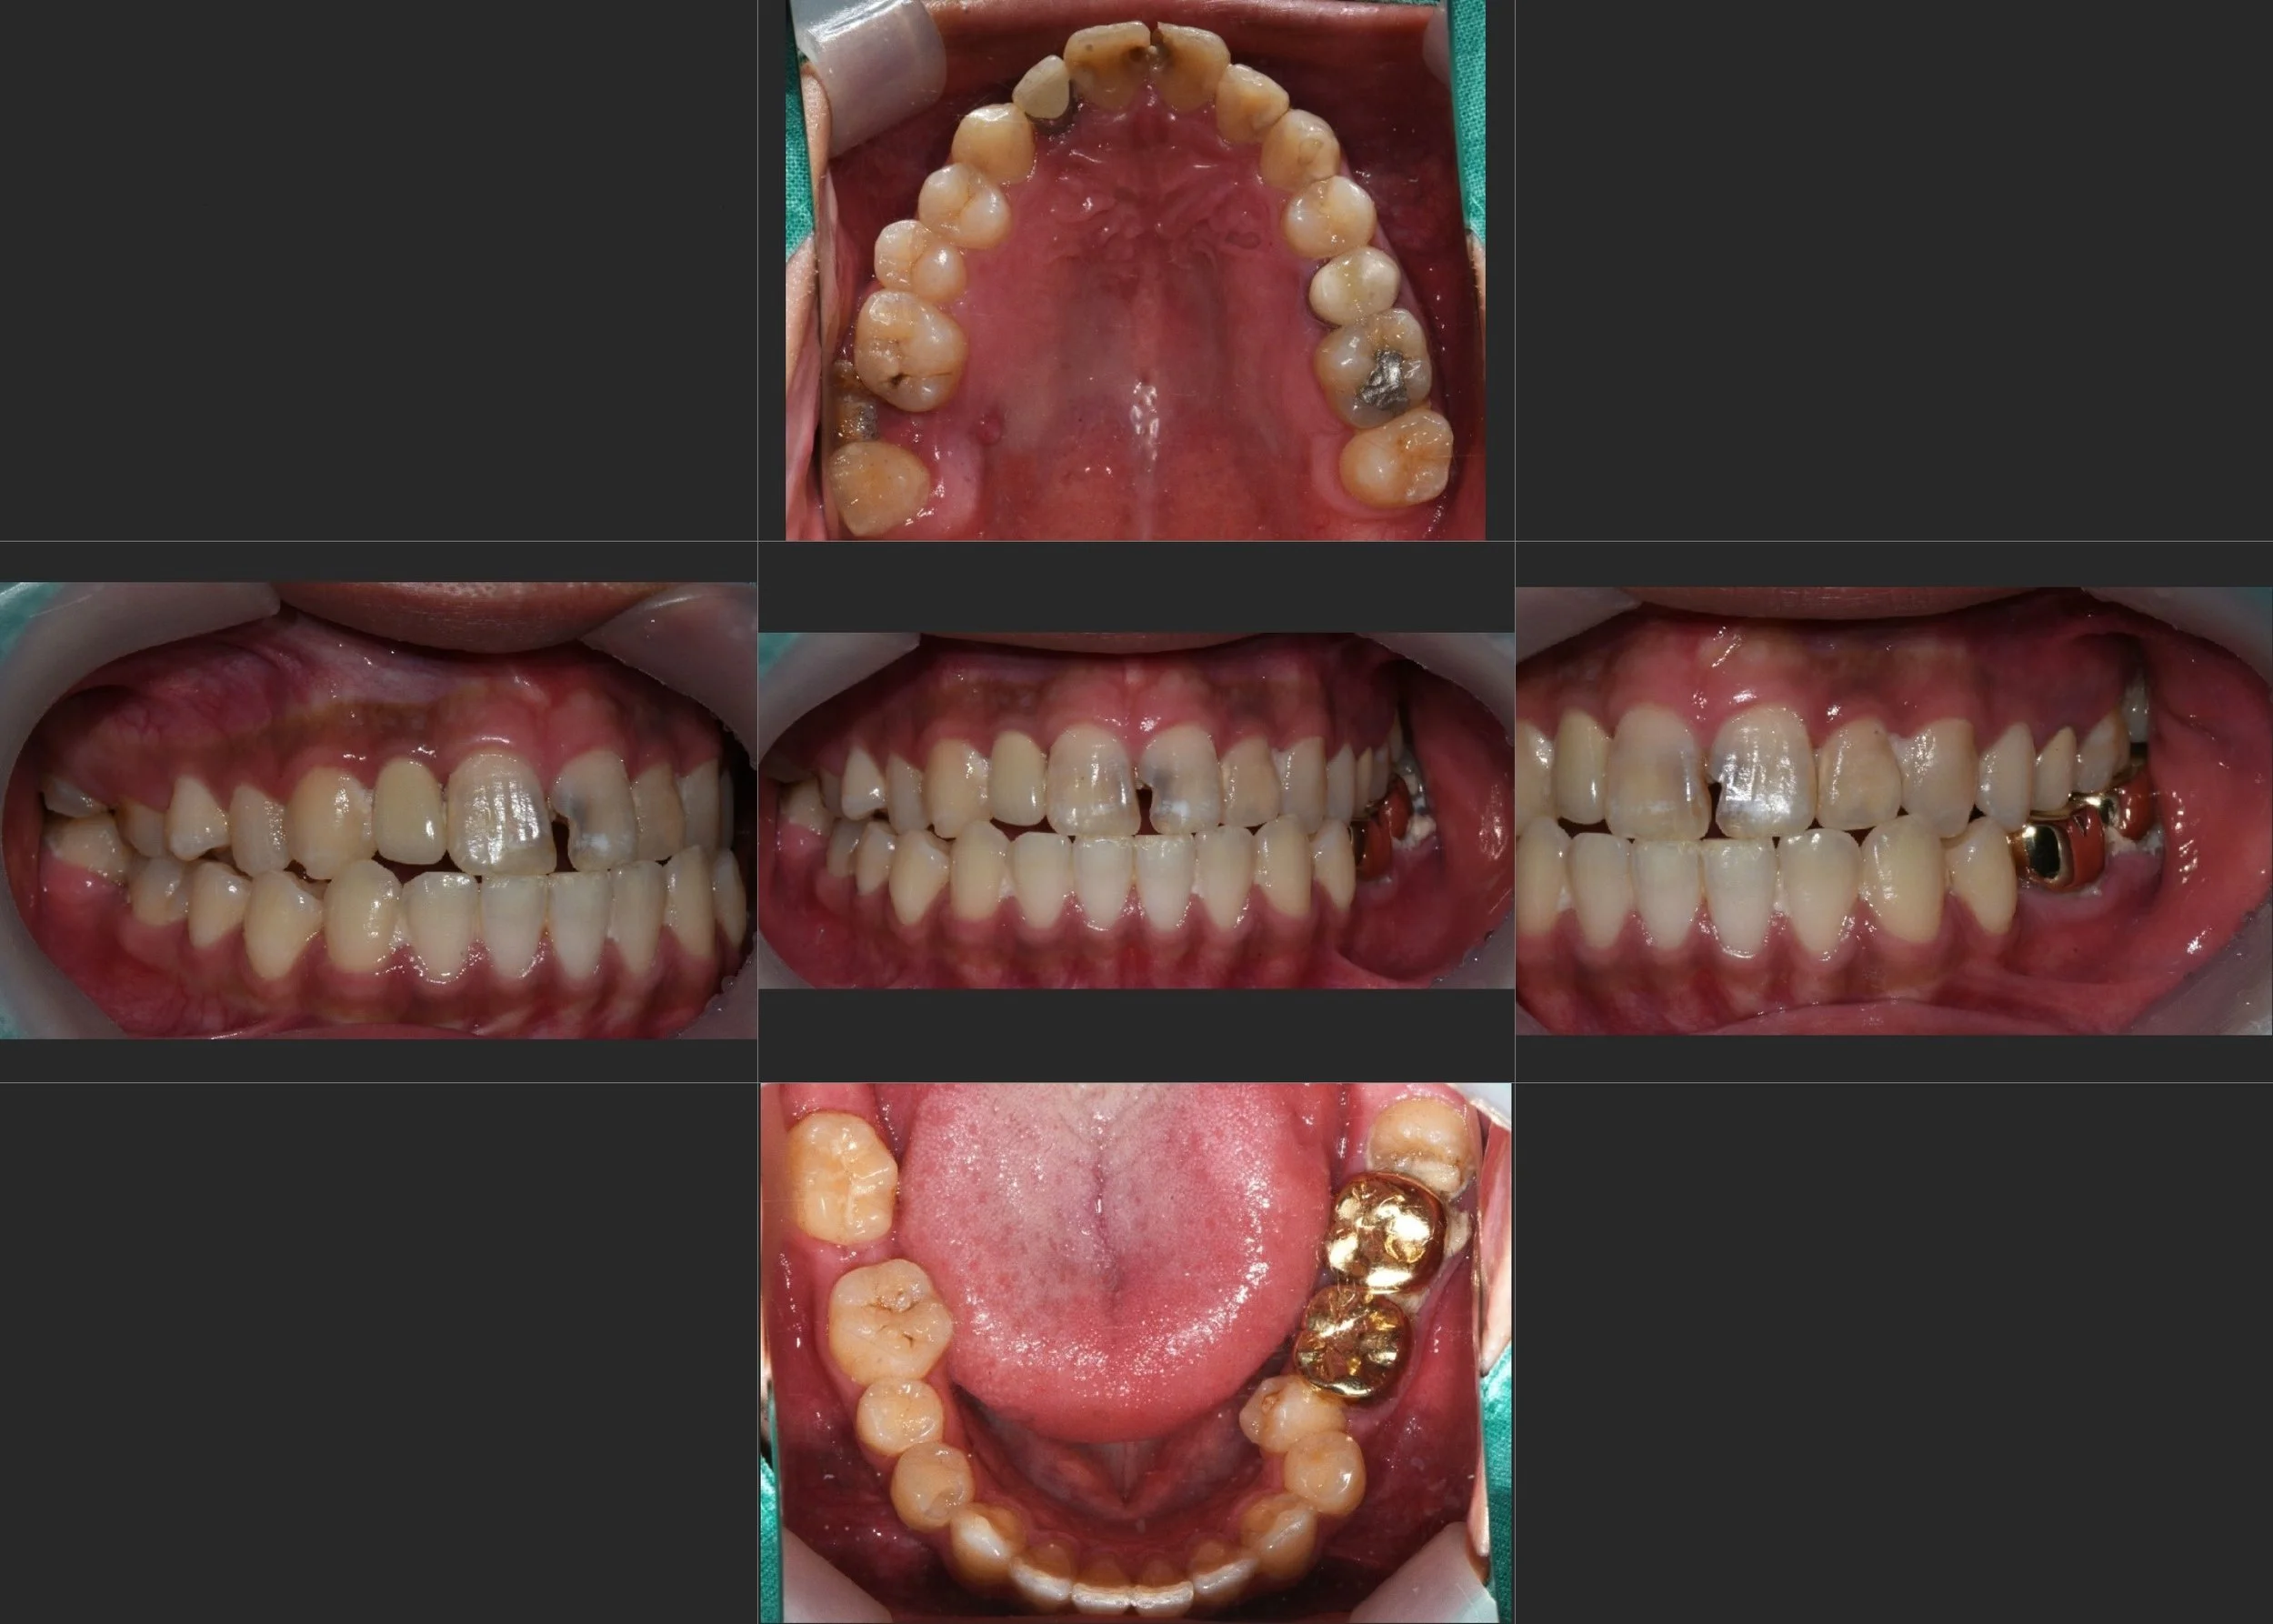

35. Comprehensive Full-Arch Transformation: Restoring Confidence in a Young Phobic Patient

Reversing the effects of generalized rampant caries and occlusal collapse in a female patient in her 20s. A tooth-preserving, implant-assisted approach focused on stable VDO elevation and overcoming social anxiety.